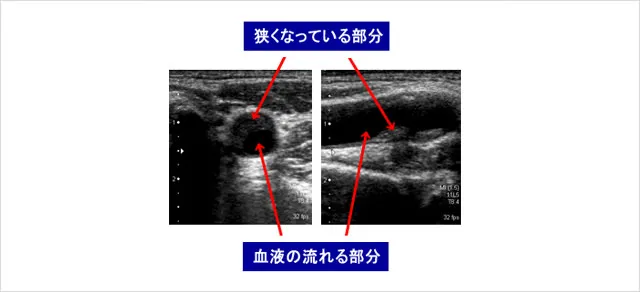

頚動脈は首の両側にありますが、ここに動脈硬化のある人は高率に心筋梗塞や脳梗塞をおこすことがわかっています。この検査では、頚動脈の動脈硬化の程度や血流を見ます。検査は痛みもなく10分程で終わり、食事や薬を止める必要もありません。

下の写真は左が頚動脈の横断面、右が縦断面で、動脈硬化のため血液の流れる部分が狭くなっています。